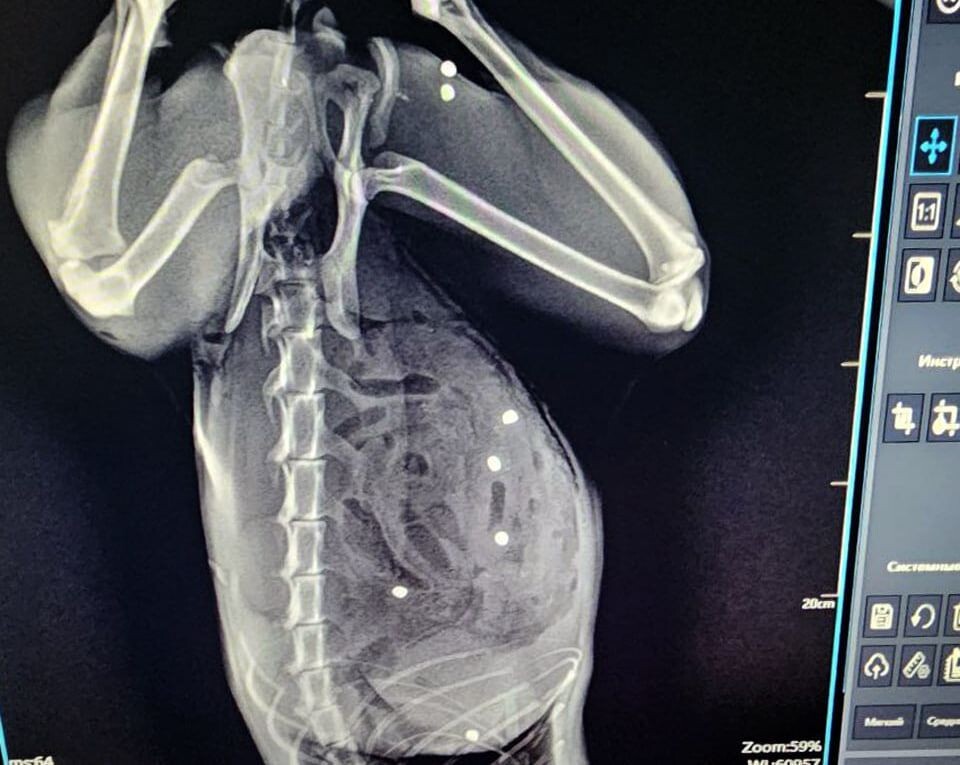

В Зеленограде ветеринары спасли пятилетнего кота Тимофея, получившего во время прогулки в частном секторе более 20 пулевых ранений. Об этом 28 ноября сообщила пресс-служба сети государственных ветклиник Москвы «Мосветобъединение».

У животного в 24 местах был пробит кишечник и в двух местах — селезенка. Также пули попали в грудную клетку и мышцы бедра. Операция длилась более трех часов. Пациента, которого считали почти безнадежным, спасли, сказано в сообщении.

«Под конец операции и кот, и я выглядели одинаково… Не скрою, горжусь собой на 100%, но ещё больше котом! Несмотря нa все усилия живодёров, котик жив!» — рассказал хирург Евгений Цыбин.